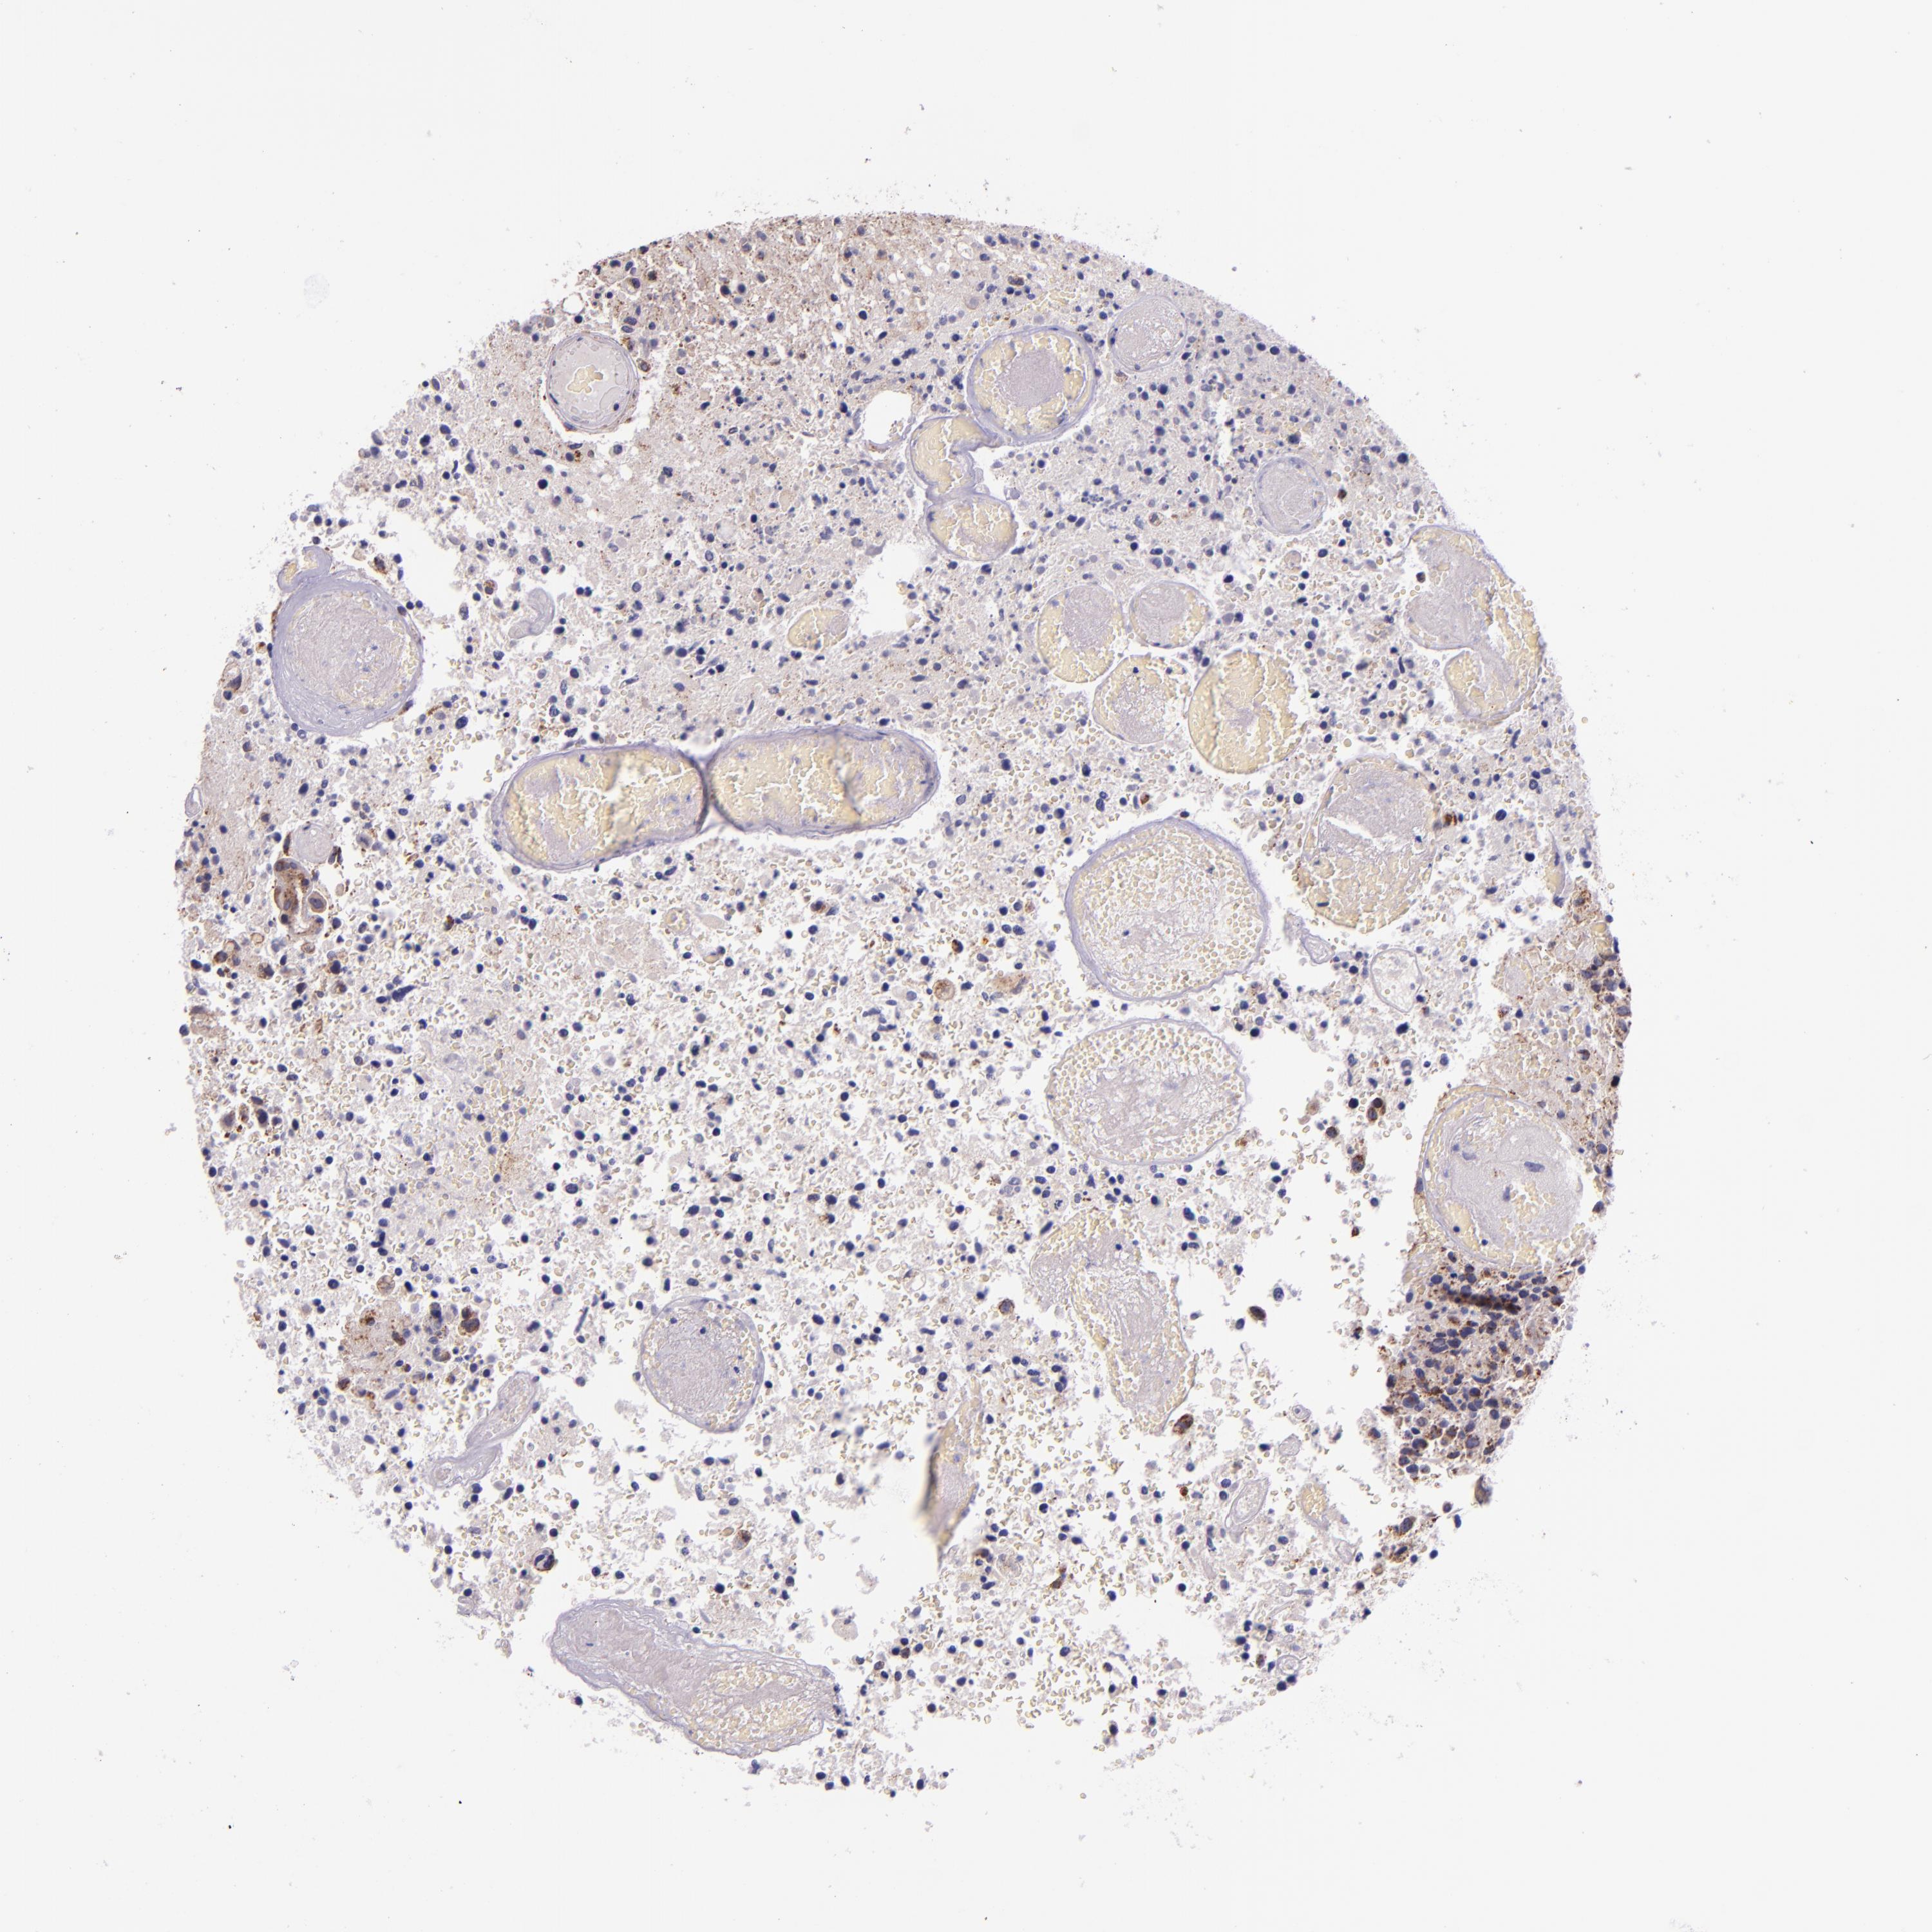

GLIOMA - Protein expressioni

A mouse-over function shows sample information and annotation data. Click on an image to view it in a full screen mode. Samples can be filtered based on level of antibody staining by selecting one or several of the following categories: high, medium, low and not detected. The assay and annotation is described here.

Note that samples used for immunohistochemistry by the Human Protein Atlas do not correspond to samples in the TCGA dataset.

Antibody stainingi

Antibody staining in the annotated cell types in the current human tissue is reported as not detected, low, medium, or high, based on conventional immunohistochemistry profiling in selected tissues. This score is based on the combination of the staining intensity and fraction of stained cells.

Each image is clickable and will lead to virtual microscopy that enables deeper exploration of all samples and also displays staining intensity scores, fraction scores and subcellular localization as well as patient and tissue information for each sample.

Antibody HPA000425

Antibody HPA002017

Staining

High

Medium

Low

Not detected

Intensity

Strong

Moderate

Weak

Negative

Quantity

>75%

75%-25%

<25%

None

Location

Nuclear

Cytoplasmic/membranous

Cytoplasmic/membranous,nuclear

Glioma, malignant, High grade

Glioma, malignant, Low grade